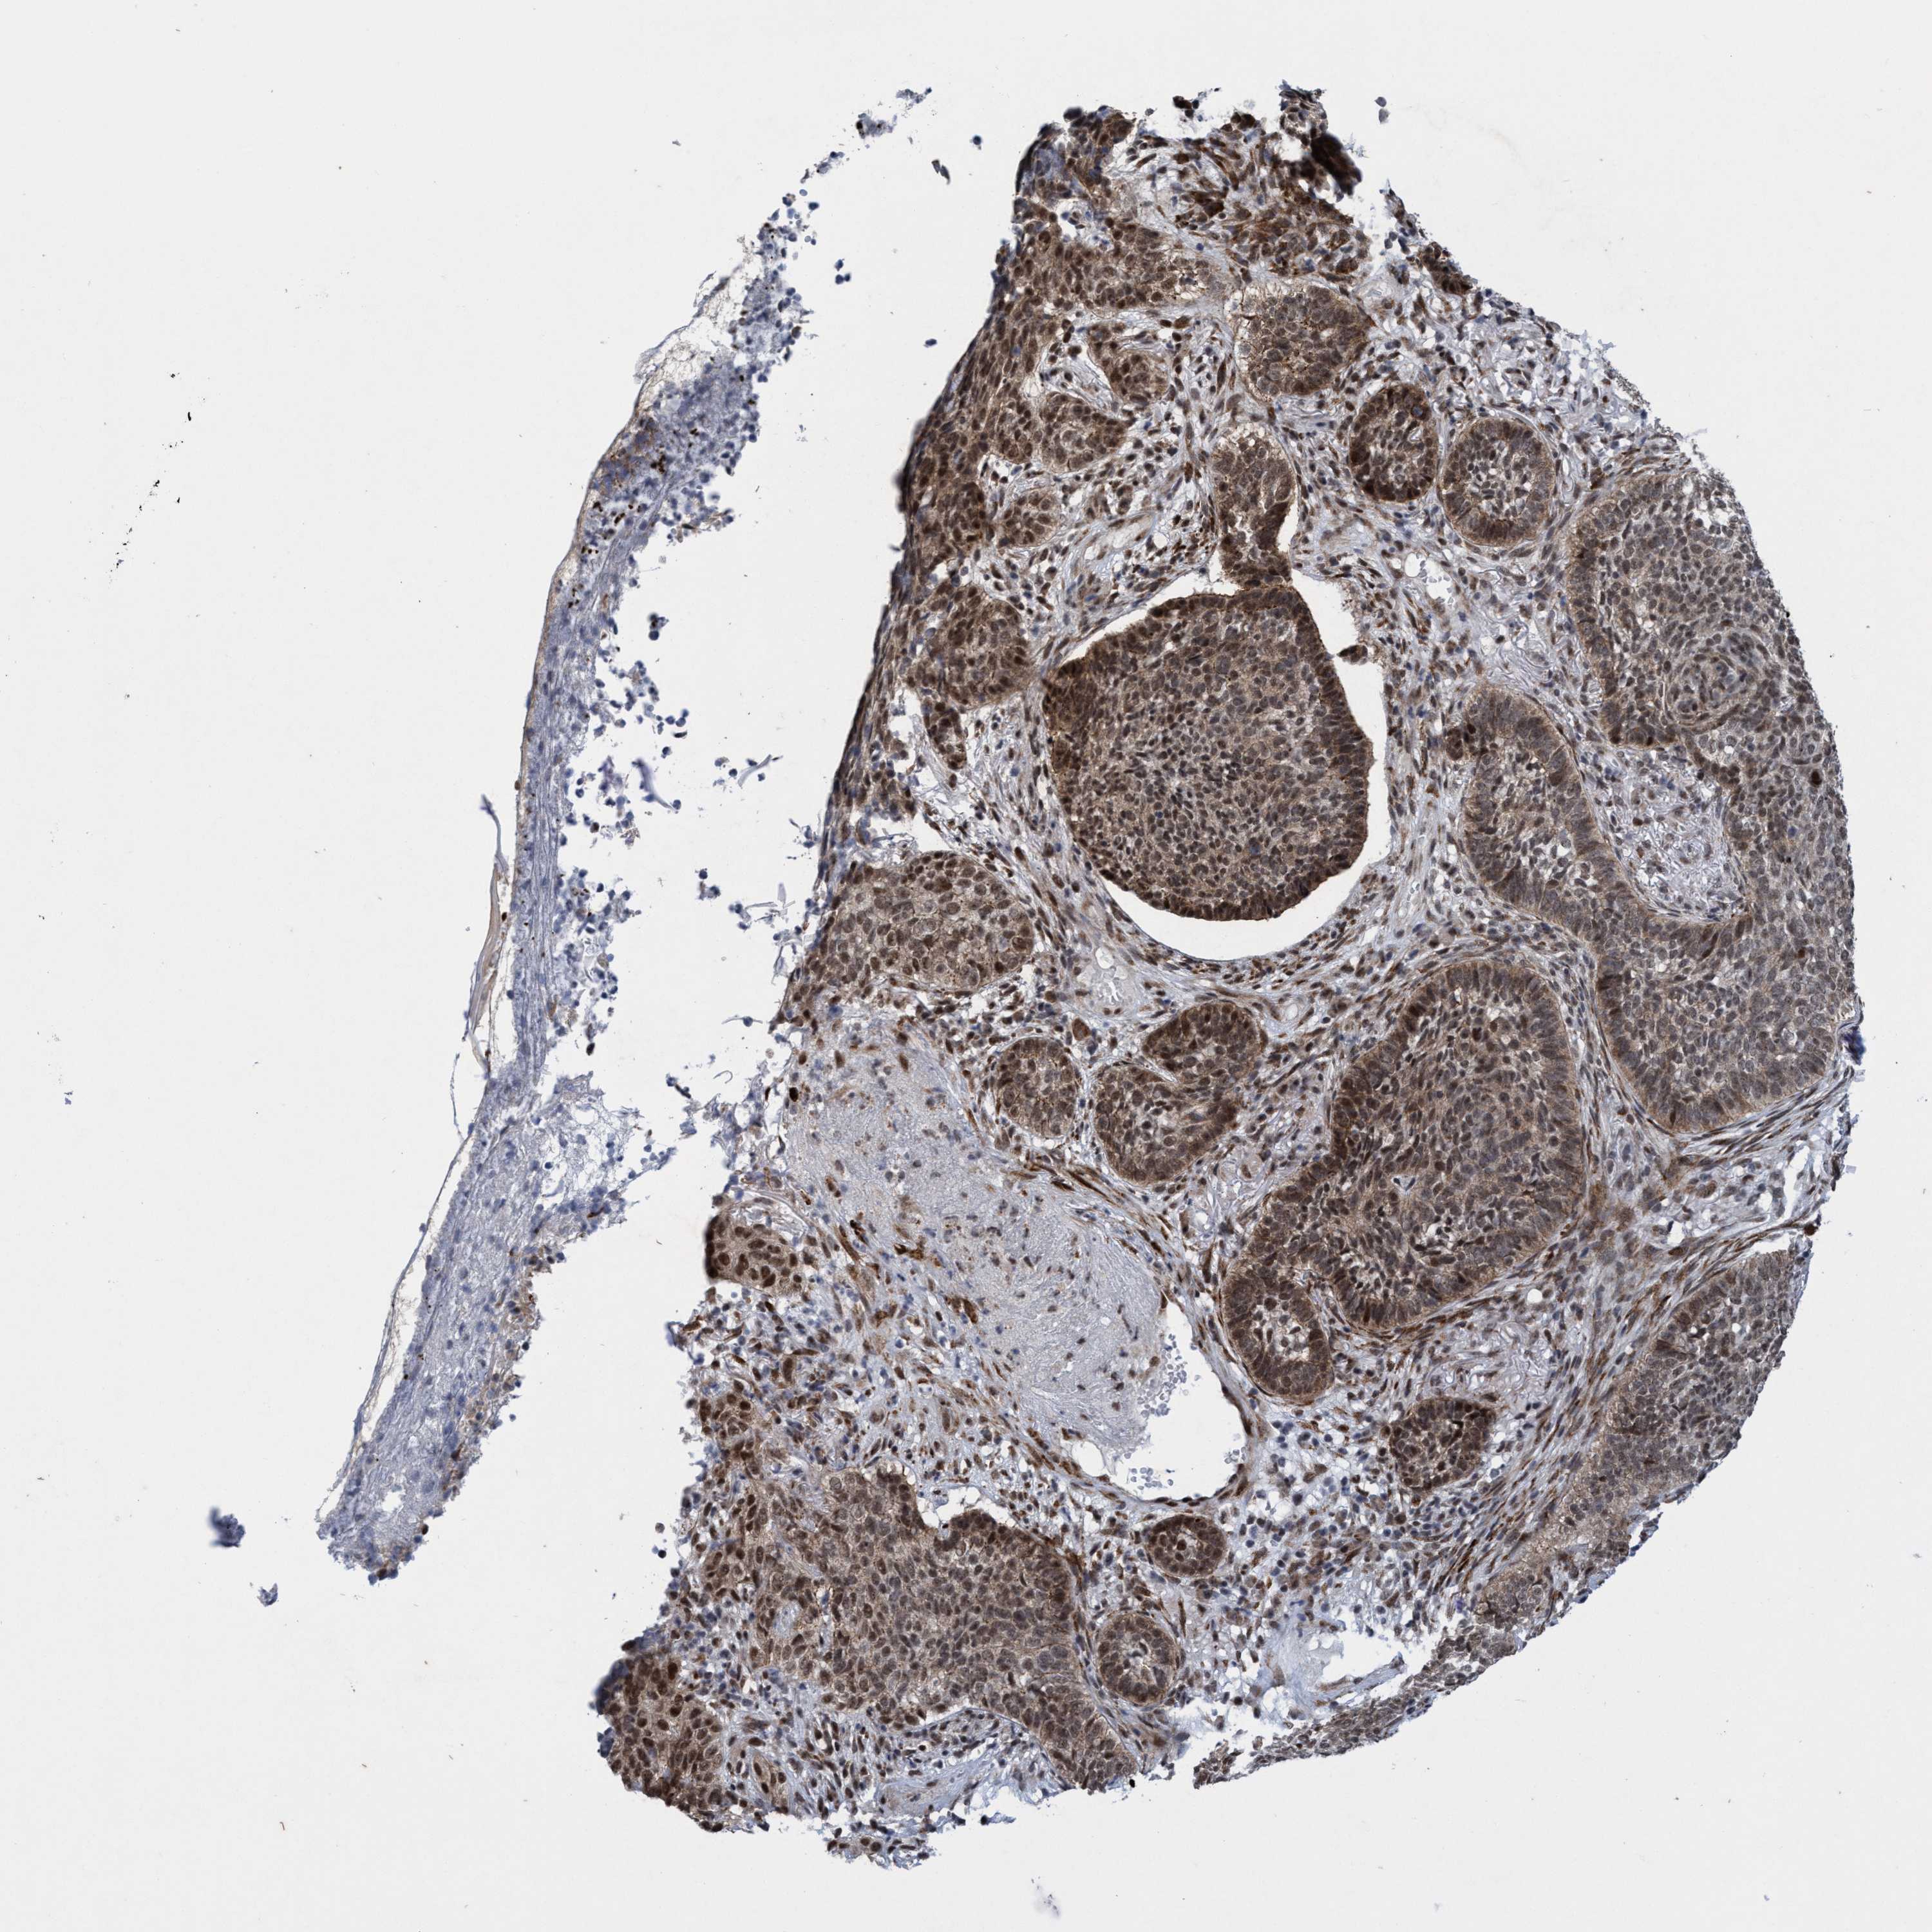

Basal cell and squamous cell cancer

SKIN CANCER - Protein expressioni

A mouse-over function shows sample information and annotation data. Click on an image to view it in a full screen mode. Samples can be filtered based on level of antibody staining by selecting one or several of the following categories: high, medium, low and not detected. The assay and annotation is described here.

Antibody stainingi

Antibody staining in the annotated cell types in the current human tissue is reported as not detected, low, medium, or high, based on conventional immunohistochemistry profiling in selected tissues. This score is based on the combination of the staining intensity and fraction of stained cells.

Each image is clickable and will lead to virtual microscopy that enables deeper exploration of all samples and also displays staining intensity scores, fraction scores and subcellular localization as well as patient and tissue information for each sample.

Antibody HPA023424

Staining

High

Intensity

Strong

Quantity

>75%

Location

Nuclear

Squamous cell carcinoma, NOS

Squamous cell carcinoma, metastatic, NOS